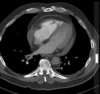

12

Q

A

Consolidación alveolar